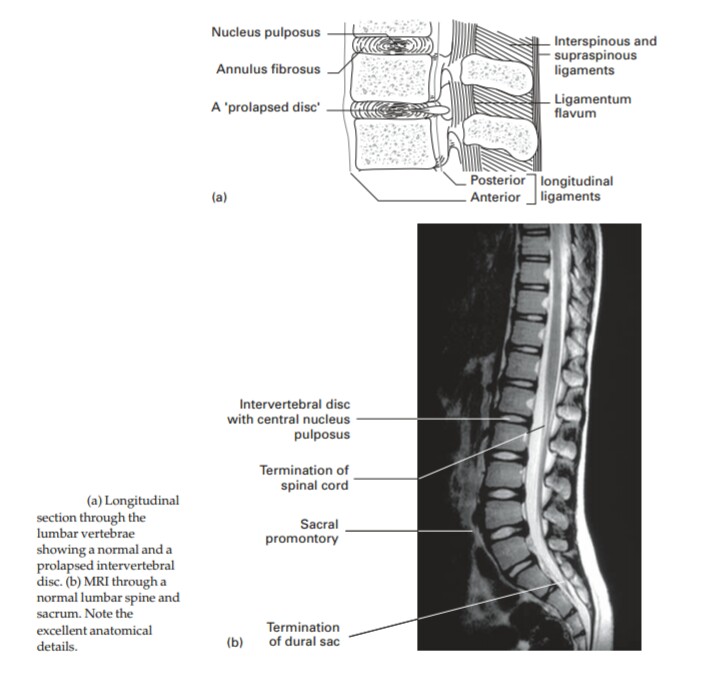

The vertebral column

The spinal, or vertebral, column is made up of thirty-three vertebrae, of

which twenty-four are discrete vertebrae and nine are fused in the sacrum

and coccyx.

In the embryo the spine is curved into a gentle C shape but, with the

extension of the head and lower limbs that occurs when the child first holds

up its head, then sits and then stands, secondary forward curvatures

appear in the cervical and lumbar region, which produce the sinusoidal

curves of the fully developed spinal column.

The basic vertebral pattern is that of a body and of a neural arch

surrounding the vertebral canal.

The neural arch is made up of a pedicle on either side, each supporting a

lamina which meets its opposite posteriorly in the midline. The pedicle

bears a notch above and below which, with its neighbour, forms theintervertebral foramen. The arch bears a posterior spine, lateral transverse

processes and upper and lower articular facets.

The intervertebral foramina transmit the segmental spinal nerves as

follows: C1–7 pass over the superior aspect of their corresponding cervical

vertebrae, C8 passes through the foramen between C7 and T1, and all sub-

sequent nerves pass between the vertebra of their own number and the one

below.

Now to consider the individual vertebrae in turn.

The lumbar vertebrae (5)

These are of great size with strong, square, horizontal spines and with

articular facets which lie in the sagittal plane.